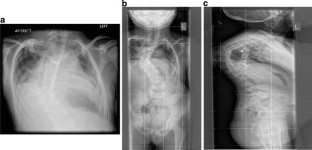

In this Grand Round, we present the case of a 7-year-old girl with a severe scoliosis and thoracic insufficiency syndrome (TIS). 3D CT reconstruction imaging demonstrated a mixed picture of fusion and segmentation abnormalities. A marked kyphoscoliosis was demonstrated at the thoraco-lumbar junction. Via a left thoracotomy, anterior excision of intervertebral discs was performed together with, interbody fusion, and in situ stabilisation of the kyphosis with double allograft (femur) strut grafts.